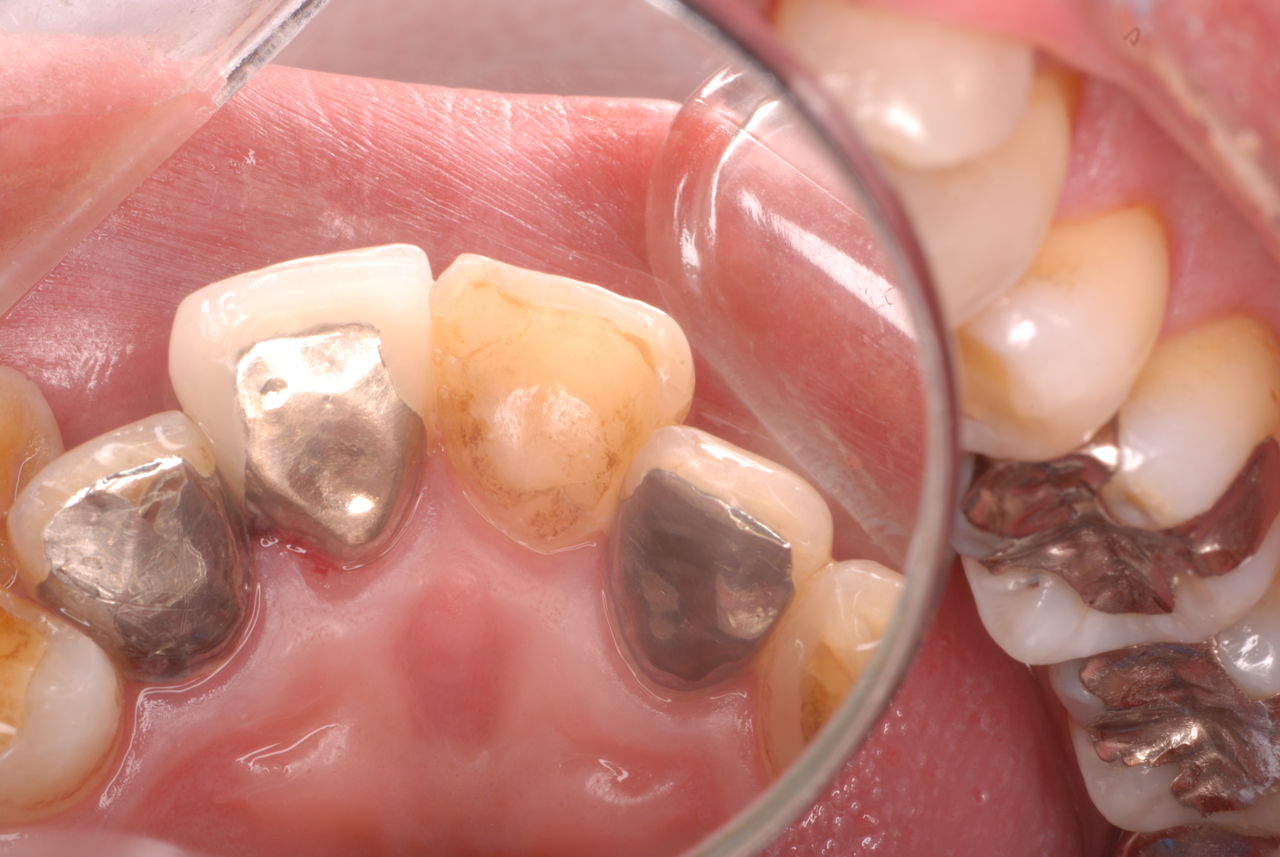

写真左下の親知らずが痛くなり抜歯しました。その後歯茎を除去して虫歯を露出させる処置を二回ほどしています。

レントゲンでは小さいですが、こう言う虫歯が一番怖いのです。

治療の成功率は極めて悪くすぐ再発しやすいのです。